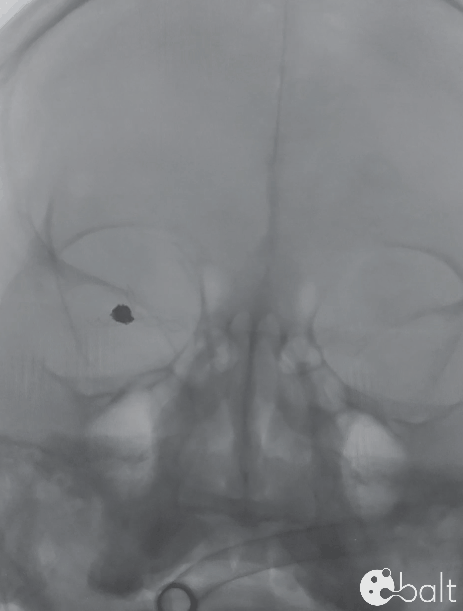

术后正位造影

术后造影显示动脉瘤致密栓塞,各分支血管血流通畅。

术后侧位造影

术后三维造影

术后CT及双容积成像显示支架头端完全覆盖动脉瘤瘤颈,支架远近端未出现打开不良。